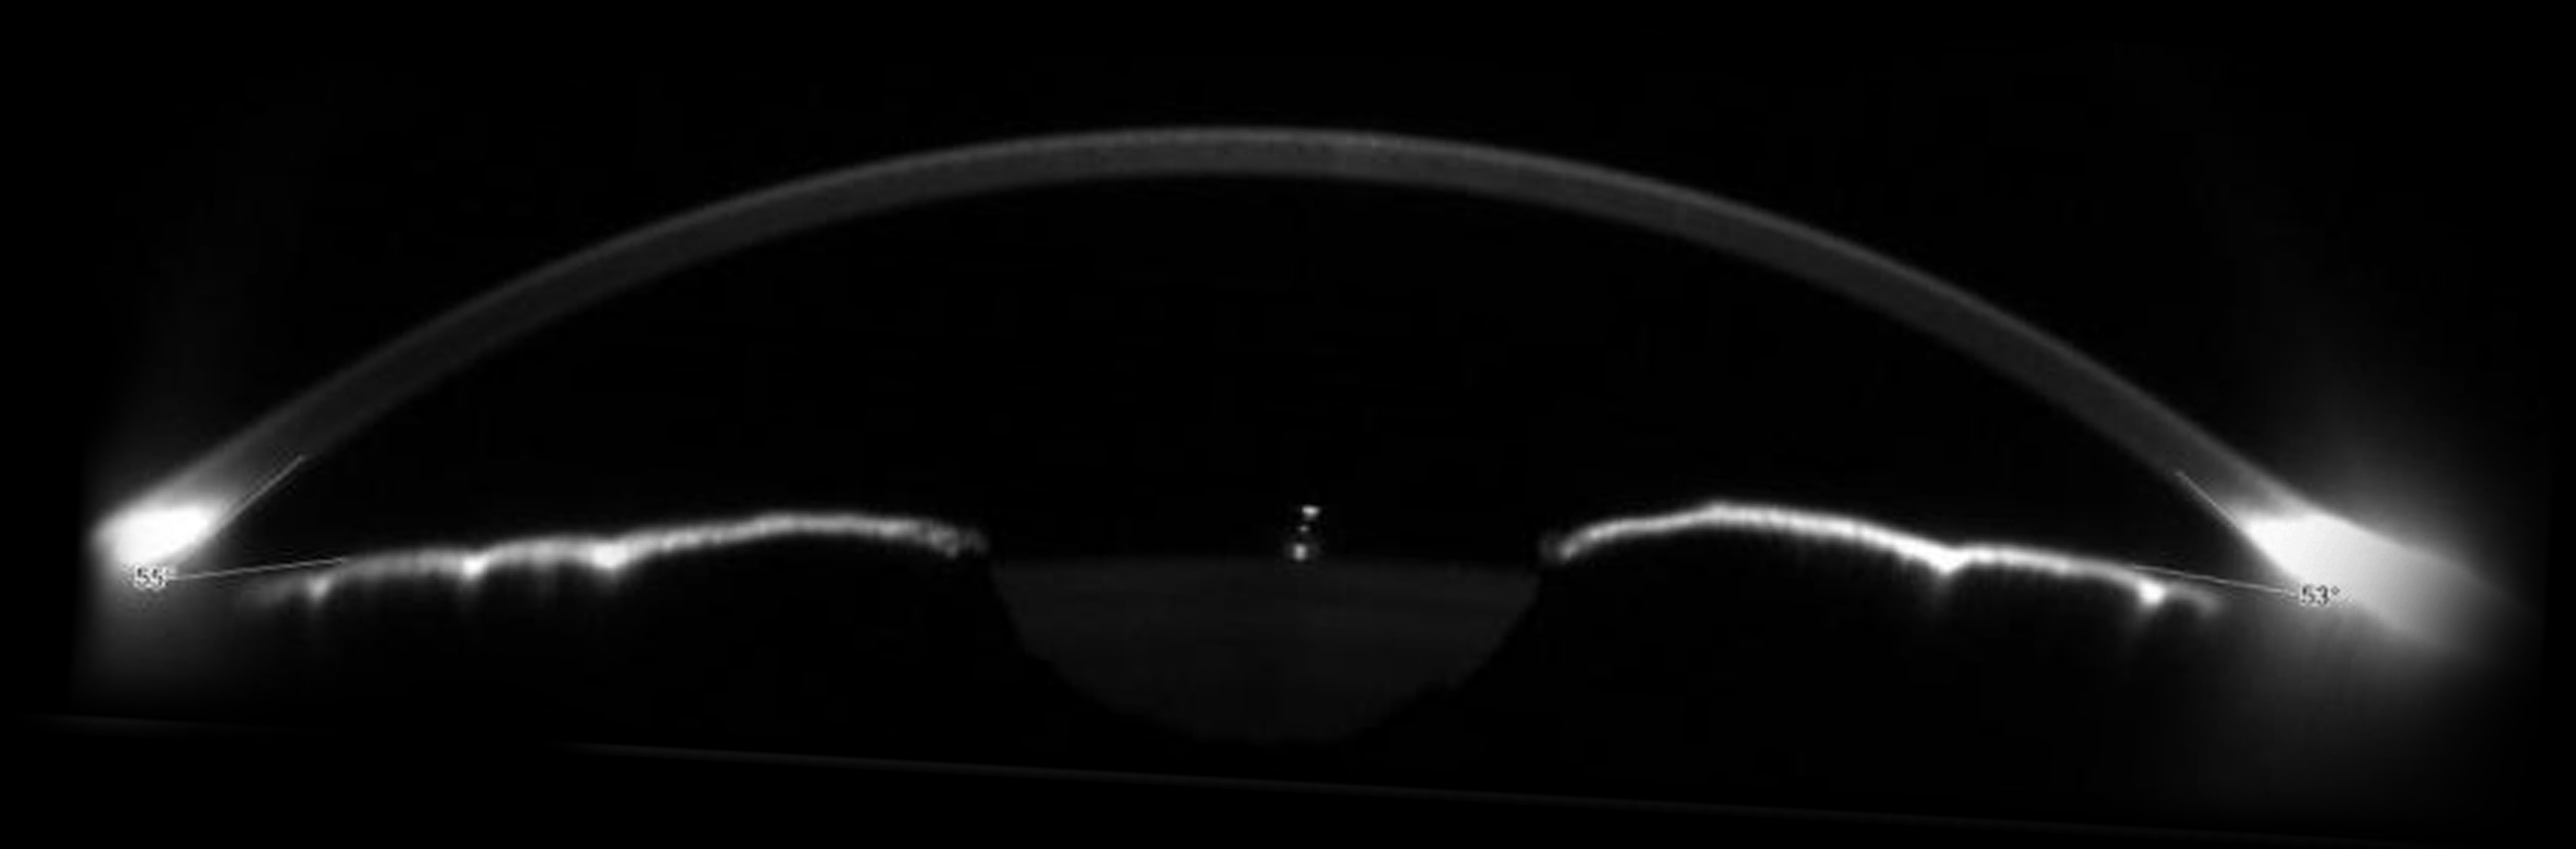

For glaucoma specialists Sirius+ enables the measurement of irido-corneal angles and pachymetry. These two values are useful in the diagnosis of the disease.